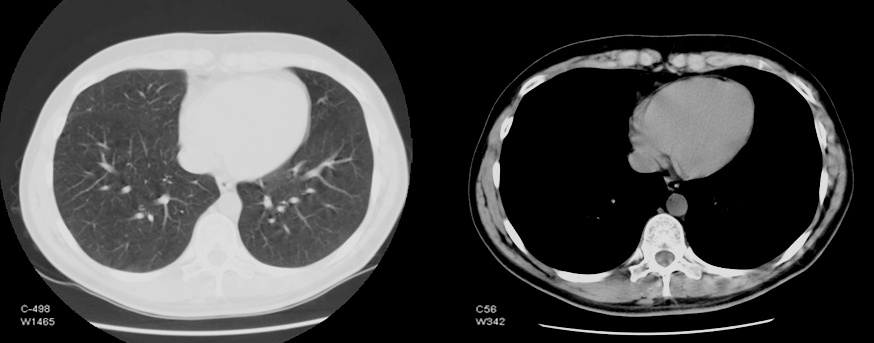

Типичная визуализация грудной клетки, полученная при помощи компьютерной томографии. Изменение параметров отображения позволяет видеть структуру разных органов.